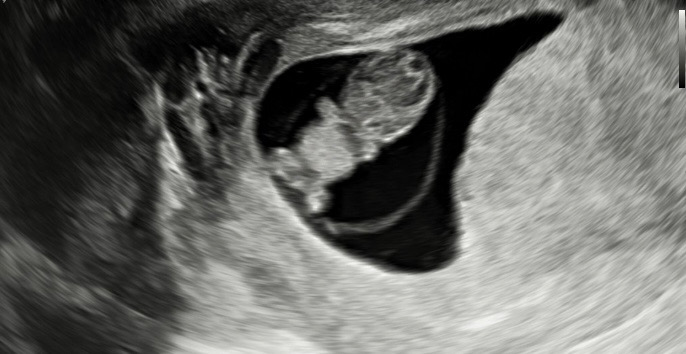

8주 5일차 초음파 보고왔어요🙂

2주만에 2.13cm ! 심박 182bpm으로 급성장 했더라구요!!!!>< 눈사람 같이 보였는데 팔다리가 뿅 나온 모습이 너무 귀엽더라구용 💖💖💖💖💖💖 젤리곰 사랑스러워요